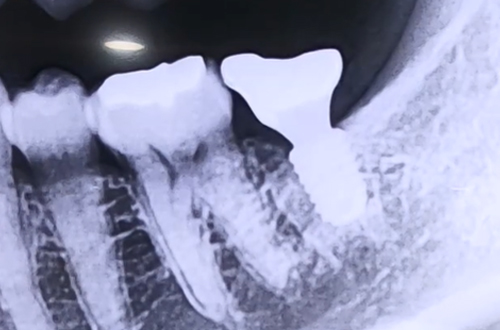

AFTER

어금니 임플란트를 위해 내원해 주신 환자분이십니다.

해당 환자분의 경우 임플란트 식립 위치와 하치조 신경이 가까우셨는데요.

어금니 임플란트 진행 시에는 그 아래쪽을 지나가는 하치조 신경의 위치를 정확하게 체크하여, 신경에 닿지 않게 하는 것이 매우 중요합니다.

따라서 CT 촬영을 통해 신경의 위치와 신경까지의 거리를 파악한 뒤 그에 맞는 길이의 임플란트를 사용하여 치료를 진행해야 합니다.